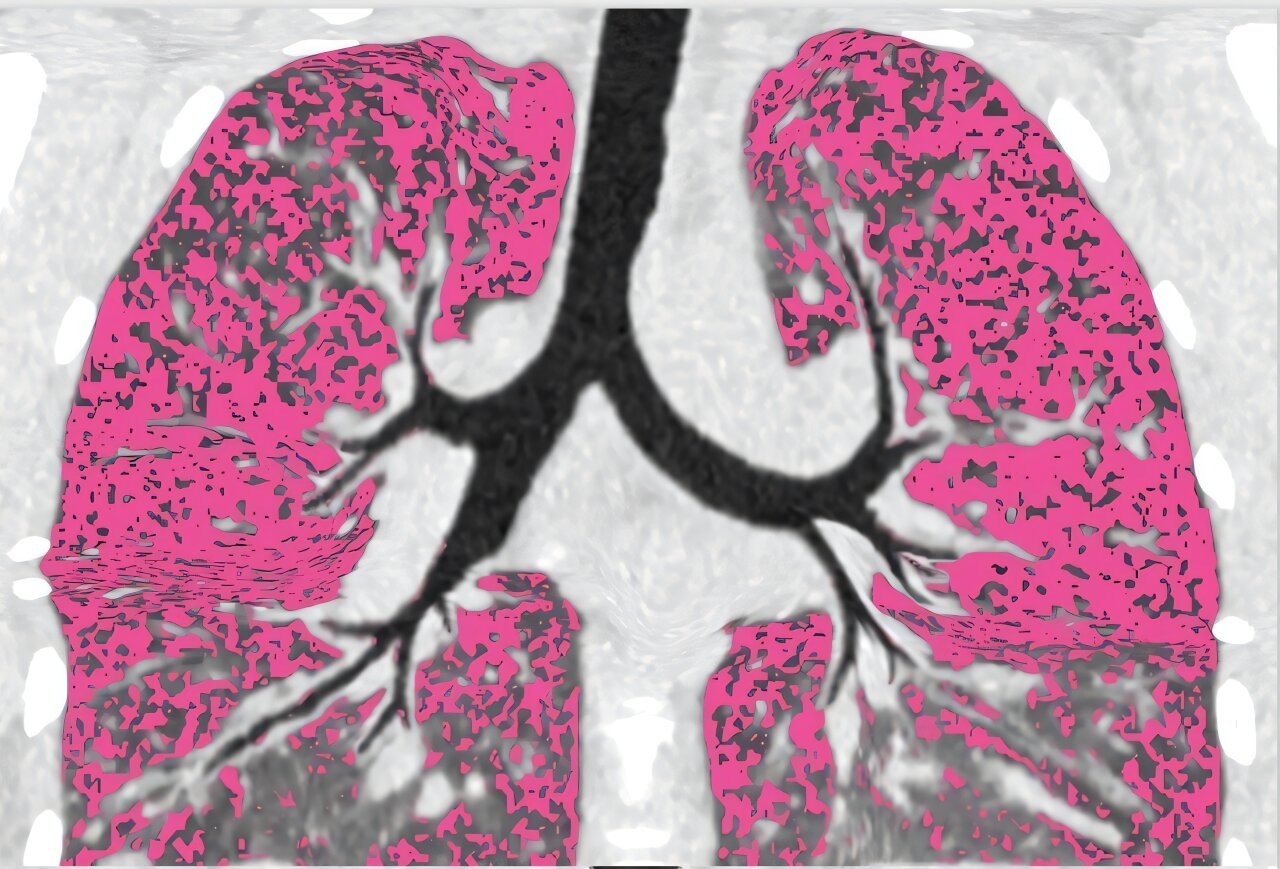

Avant que les participants à l’étude ne commencent sur des modulateurs, les chercheurs sont entrés dans les poumons des patients avec des caméras minces appelées bronchoscopes. Ils ont échantillonné des régions qui différaient par la quantité de dommages, d’infection et d’inflammation.

Ils ont ensuite revu les mêmes zones pulmonaires un an après le traitement pour voir où l’infection restait et quelles caractéristiques pulmonaires étaient liées à une infection persistante.

Durfey a poursuivi: « Cependant, les personnes qui sont restées infectées avaient une infection et une inflammation partout où nous regardons, y compris les zones pulmonaires avec très peu de dégâts. »

Ces résultats suggèrent que les dommages pourraient ne pas être la principale cause de la persistance des infections et soulever que la fonction pulmonaire chez les personnes infectées bactériennes pourrait continuer de se détériorer.